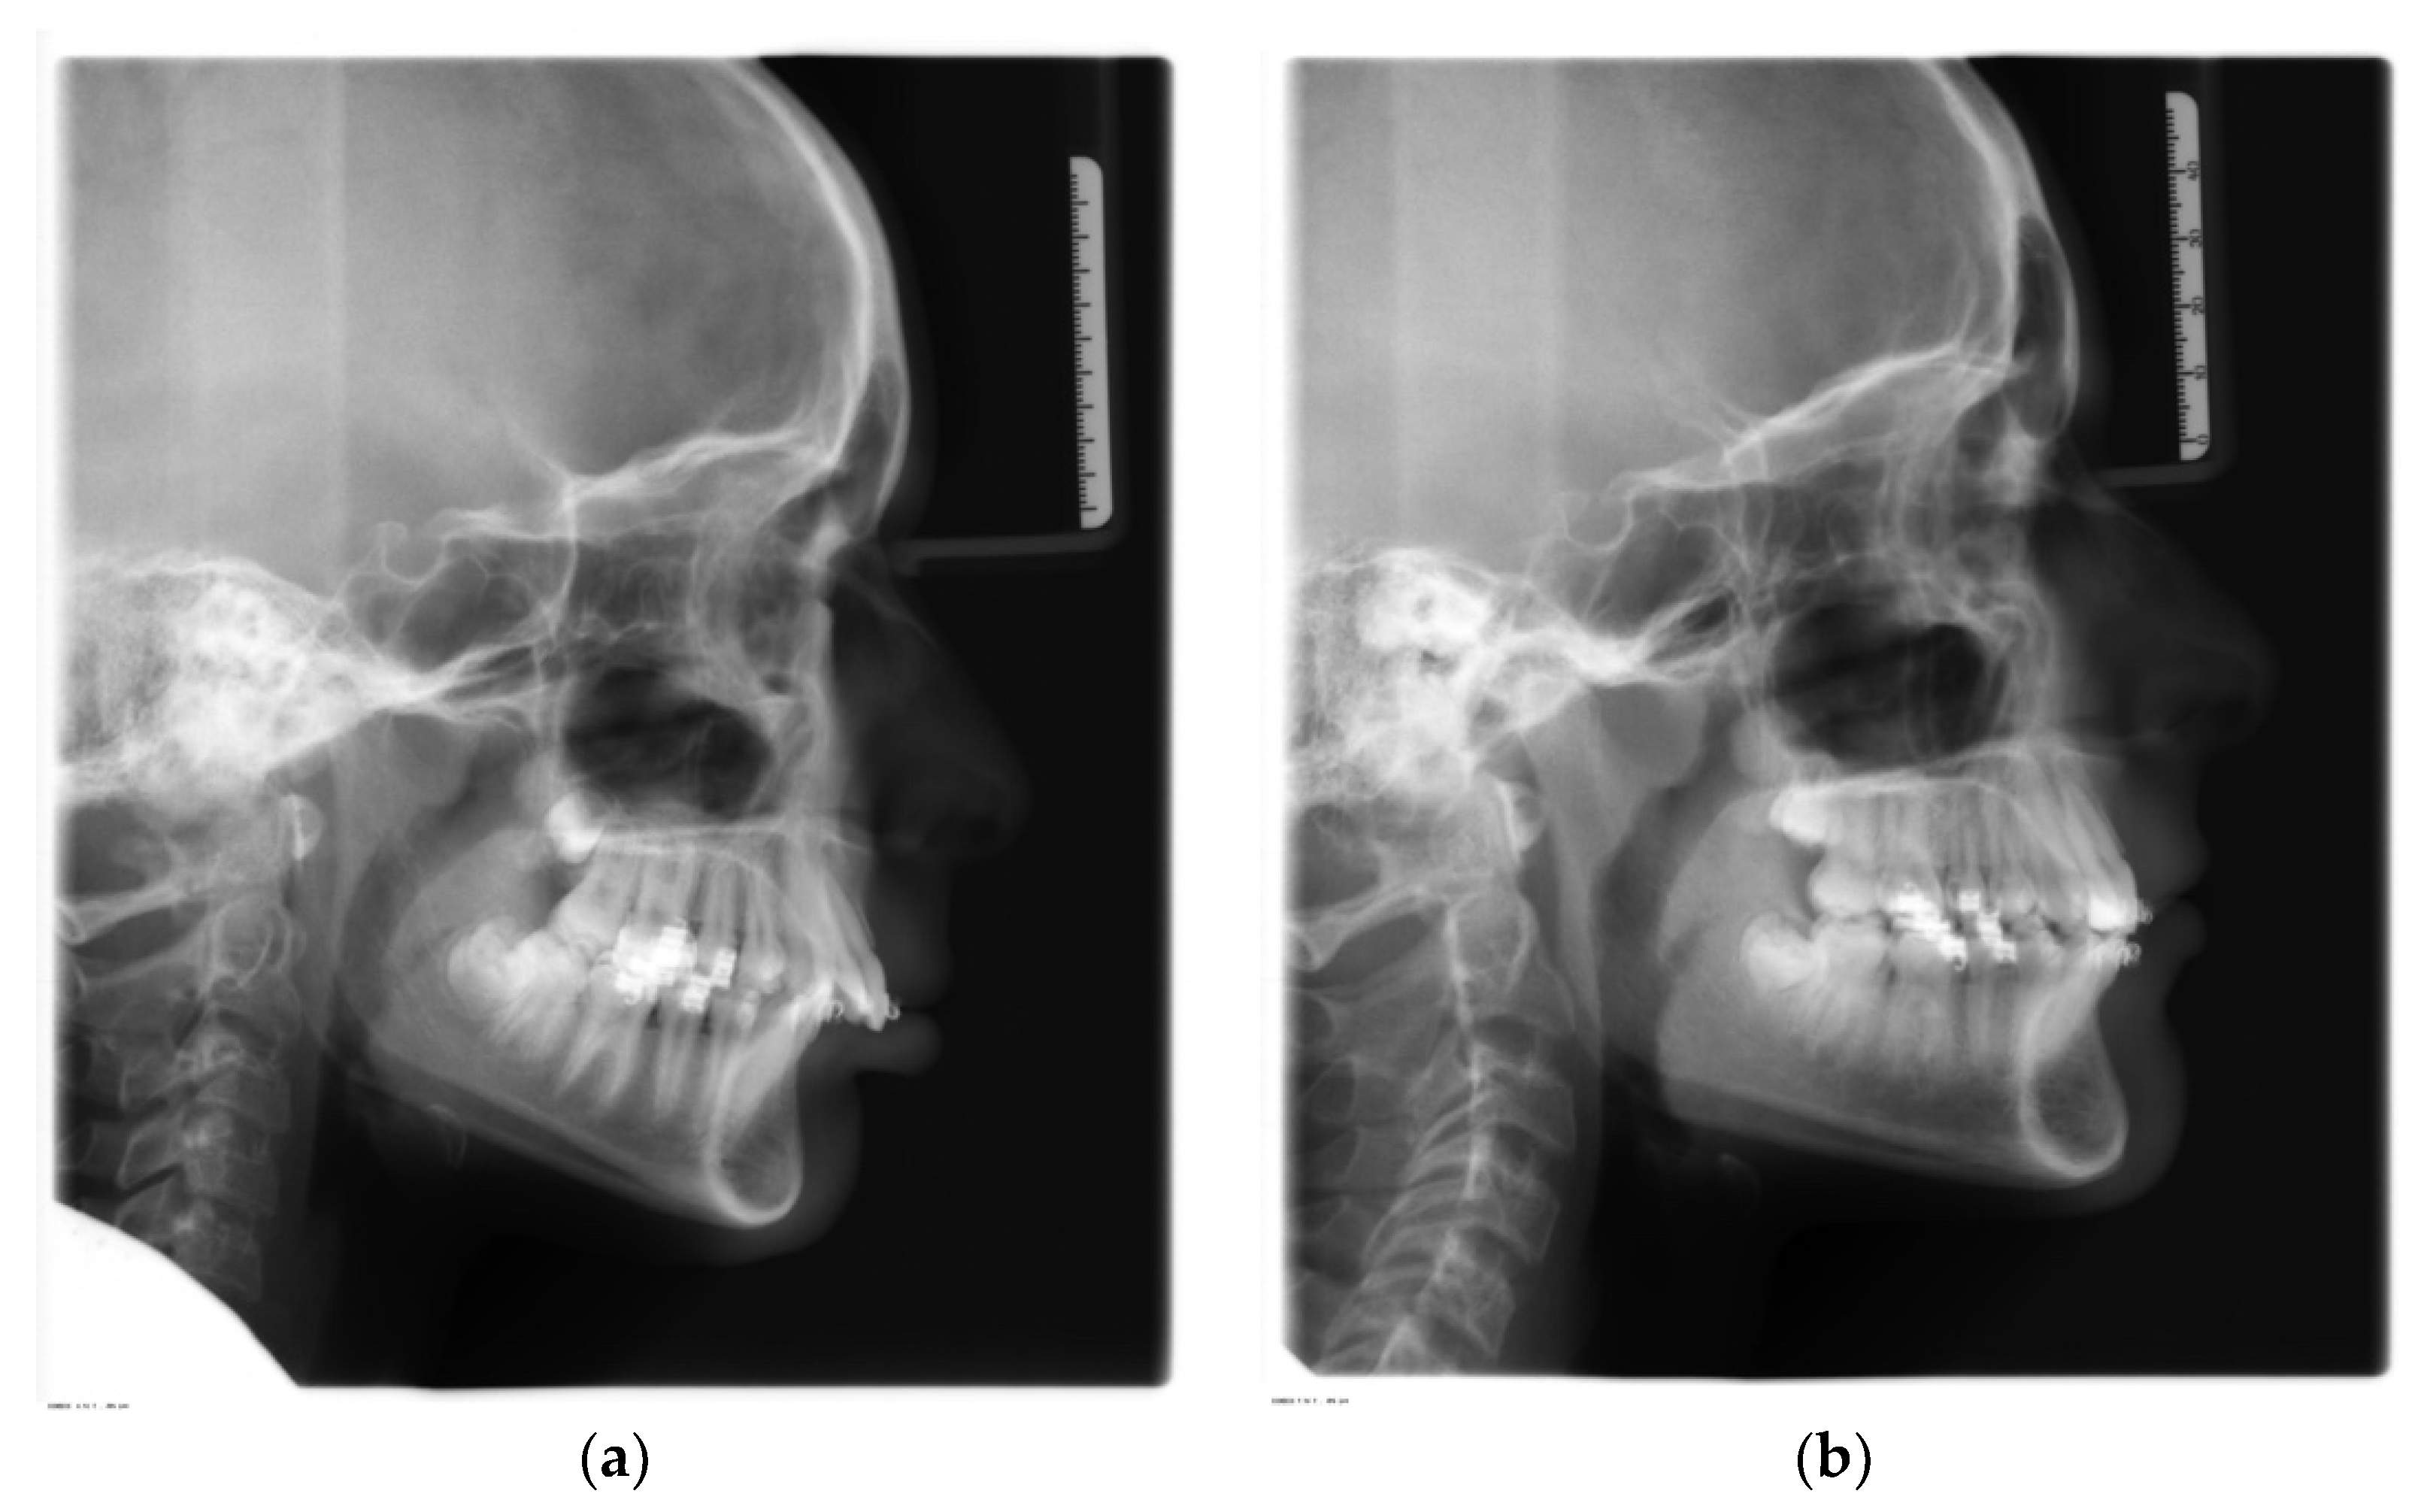

- SNA (°): angle between sella, nasion, and subspinale point A. It indicates the antero-posterior position of the maxilla relative to anterior cranial base (Figure 1, 1);

- SNB (°): angle between sella, nasion, and supramentale point B. It indicates the antero-posterior position of the mandible to anterior cranial base (Figure 1, 2);

- ANB (°): angle resulting from the difference between the SNA and SNB angles, which provide an indication of the sagittal skeletal relationships (Figure 1, 3);

- Wits (mm): is the measure of the segment Ao-Bo where Ao and Bo indicate respectively the projection of point A and point B on the occlusal plane (Figure 2, a);

- SN-Occlusal Plane (°): angle between the cranial base (SN) and the occlusal plane (Figure 1, 4);

- SN-Palatal Plane (°): angle between the cranial base (SN) and the palatal plane (Figure 1, 5);

- SN-Mandibular Plane (°): angle between the cranial base (SN) and the mandibular plane (Figure 1, 6);

- Palatal Plane-Mandibular Plane (°): angle between the bispinal plane and the mandibular plane, expressing intermaxillary divergence (Figure 1, 7);

- Co-Gn (mm): distance from condylion to anatomic gnathion, expressing total mandibular length (Figure 2, b);

- Co-Go (mm): distance from condylion to gonion, expressing the height of the mandibular ramus (Figure 2, c);

- Co-Go-Me (°): mandibular angle (Figure 1, 8);

- Overjet (mm): parameter indicating the measurement of the distance in the sagittal plane between the incisal margin of the upper incisors and the vestibular surface of the lower incisors (Figure 2, d);

- Overbite (mm): distance in the vertical plane between the incisal margin of the upper and lower central incisors (Figure 2, e);

- Molar relationship (mm): distance between the projections in the occlusal plane of the point of contact between the first permanent molars and the adjacent mesial tooth (second deciduous molar or second premolar) (Figure 2, f);

- Inc. Sup.-Pal. Pl. (°): angle expressing the inclination of the axis of the upper central incisor relative to the palatal plane (Figure 1, 9);

- Inc. Inf.-Mand. Pl. (°): angle expressing the inclination of the axis of the lower central incisor relative to the mandibular plane (Figure 1, 10);